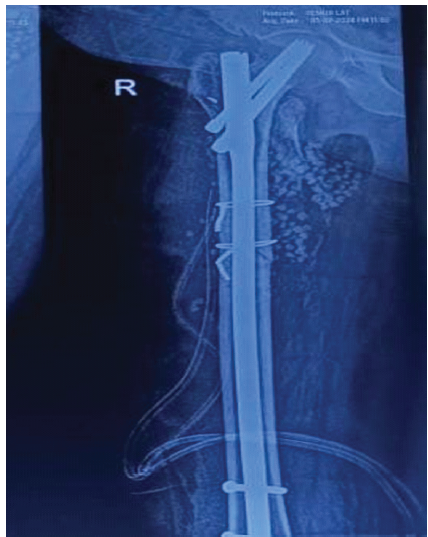

In the setting of immediate post-operative SSI and the X-ray finding, the diagnosis of retained mop/Gossypiboma was made. After optimization of her physiological parameters, the wound was debrided under anesthesia. The mop was removed. A thorough wound wash was given. The dead space and the surgical site were then filled with Stimulan (absorbable calcium sulfate antibiotic carrier) mixed with Vancomycin and Amikacin (Fig. 3). The wound was closed under a deep and a superficial suction drain.

Figure 3: Radiograph showing stimulan beads filled in the void after mop removal.